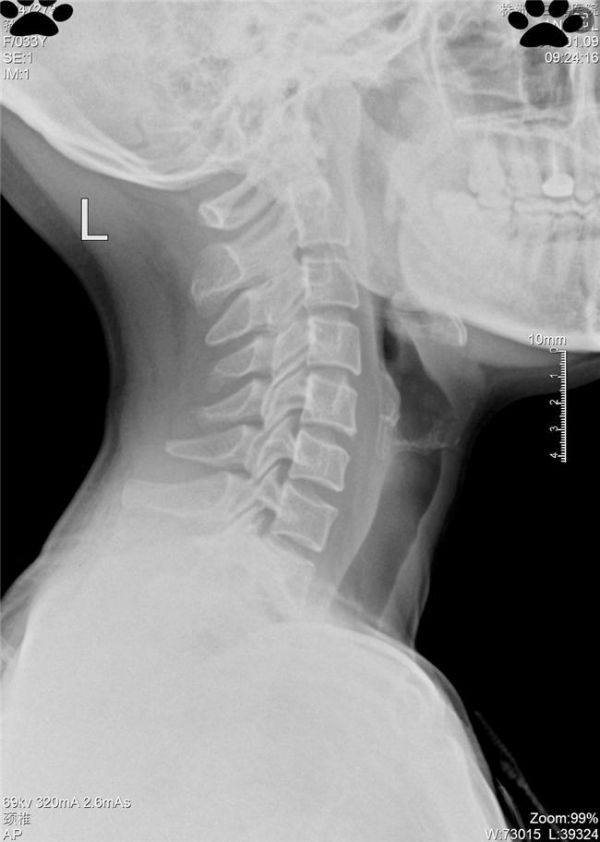

湖南白领孙先生因长期伏案导致颈椎反弓,在使用H9护颈深睡枕配合康复训练后,MRI影像显示椎间隙恢复至正常范围。该案例经@健康中国 转发,引发微博话题**#年轻人的颈椎快不行了#** 累计阅读量破2亿。